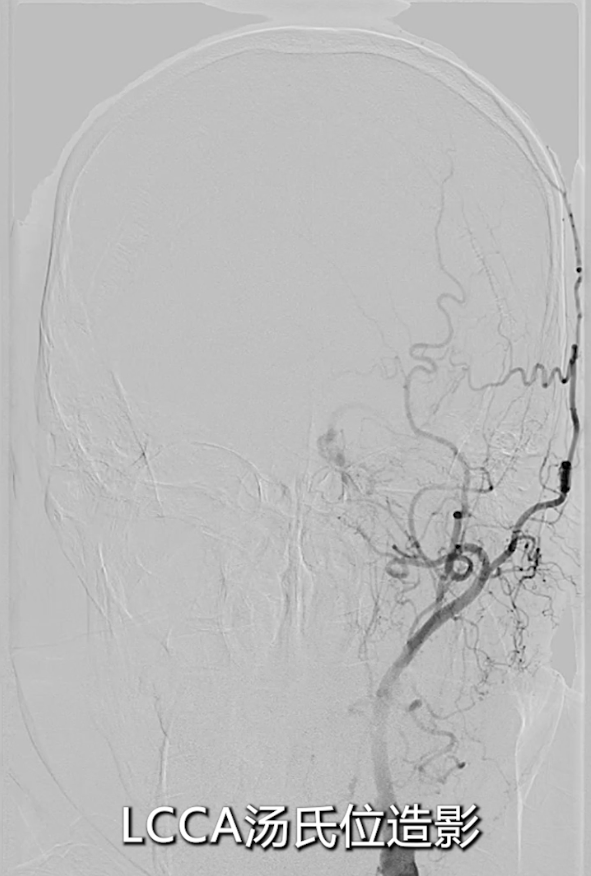

左侧颈总动脉造影:明确左侧颈内动脉闭塞,侧支循环通过颈外动脉部分供应颅内血流;

右侧颈总动脉造影(正位、汤氏位、侧位):明确右侧颈内动脉重度狭窄,病变远端直径5mm、近端直径8mm,长度约30mm,远端锚定区条件理想。

最终造影:支架血流通畅,颅内血流较术前明显改善(侧位及汤氏位对比显著);